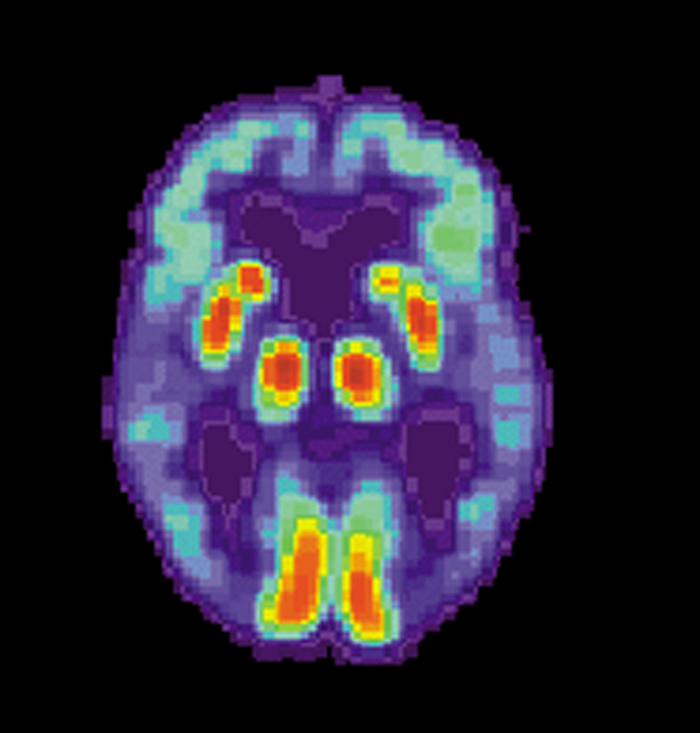

(神秘的地球uux.cn报道)据EurekAlert!:载脂蛋白Eε4等位基因(这是晚发型阿尔茨海默病的主要遗传风险因子)的女性携带者会比男性罹患阿尔茨海默病的风险更大吗?《美国医学会杂志-神经内科学》上新发表的文章对这一问题进行了检查。

一个流行的观点是,携带载脂蛋白Eε4等位基因(APOE)拷贝的女性发生阿尔茨海默病的风险要比携带同样拷贝数该基因的男性更大。